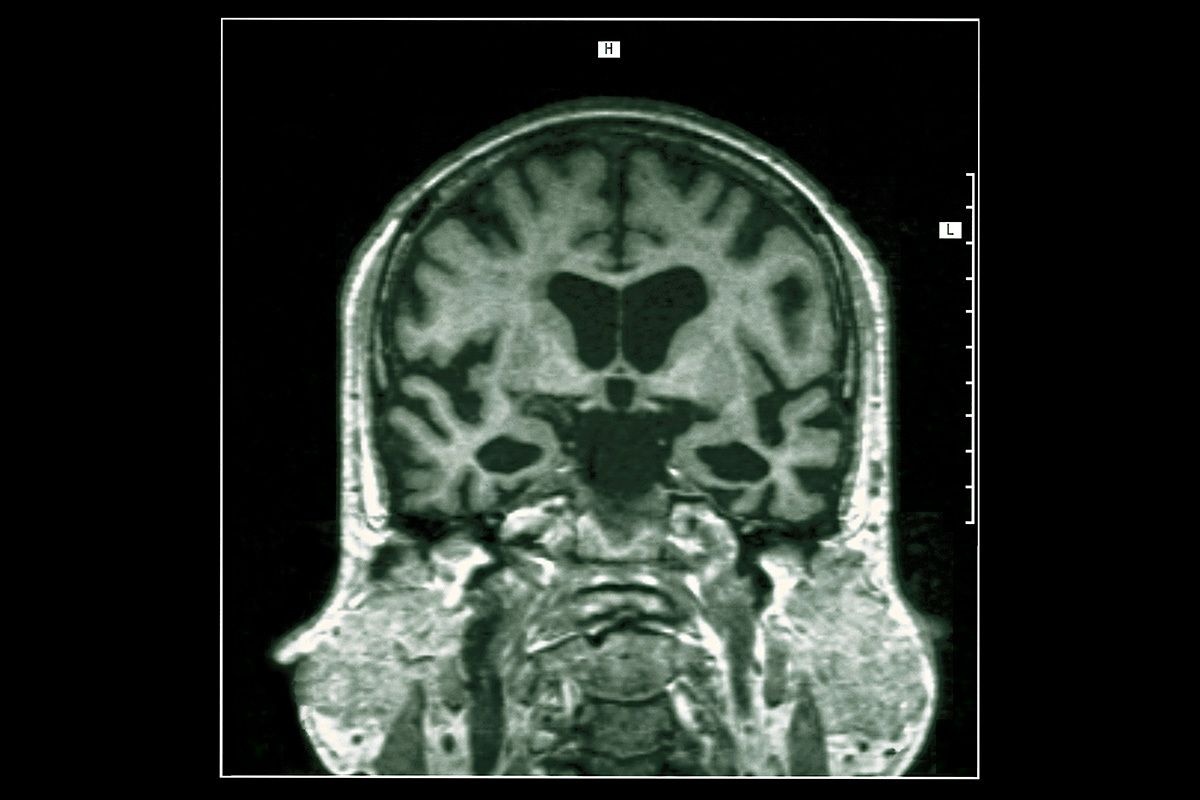

一般的にアルツハイマー病はアミロイドβというたんぱく質によって引き起こされるといわれているが、同書はそうでなく、多数の疫学研究(病気などに関して人間の集団を対象にした調査・分析)論文を紹介しながら、多くの人が感染するヘルペスウイルスが原因だと指摘している。

現在、アルツハイマー認知症の原因はアミロイドβ、というのはほぼ常識になっているが、これは1980年代にアルツハイマー認知症の病変といわれた脳内の老人斑がアミロイドβで構成されていることが分かり、90年代になって「アミロイドカスケード仮説」として広く支持されてきたからだ。

実は、同時期にカナダの神経病理学者が、人に感染したヘルペスウイルスが記憶に関わる大脳辺縁系に侵入・感染して炎症を起こしていたことから、アルツハイマー病は単純ヘルペスウイルスによる感染症が原因であるという仮説を唱えたのだが、残念ながらこちらはあまり注目されなかった。

「2016年にドイツの神経病理学者ブラーク夫妻らは、ドイツの大学病院でアルツハイマー認知症の脳の病理解剖2332例を調べました。驚くべきその内容は、(アルツハイマー病を)発症する前からアミロイドβよりも先に、変異したタウというたんぱく質が蓄積し始め、その最終段階でアルツハイマー認知症が発症するという事実でした。つまり、アルツハイマー認知症が発症するのは、アミロイドβが原因ではなく、変異したタウの蓄積の結果なのです。さらに症状の進行も、変異タウの蓄積と比例していたのです」